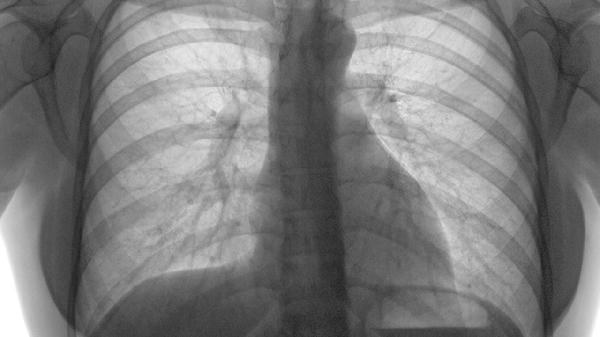

肺结节钙化意味着是什么意思

肺结节钙化通常意味着结节内部出现钙盐沉积,可能与陈旧性炎症、结核感染或良性病变有关。肺结节钙化的原因主要有陈旧性肺结核、组织胞浆菌病、错构瘤、肺内淋巴结钙化、尘肺病等。

发现肺结节钙化后应完善胸部CT随访,对比历史影像判断钙化稳定性。避免吸烟及接触二手烟,保持室内空气流通。适量进行有氧运动如快走、游泳,增强肺功能。饮食注意补充维生素D和钙质,每日摄入300毫升牛奶或等效乳制品。若出现新发咳嗽、胸痛或钙化结节增大,需及时呼吸科就诊。